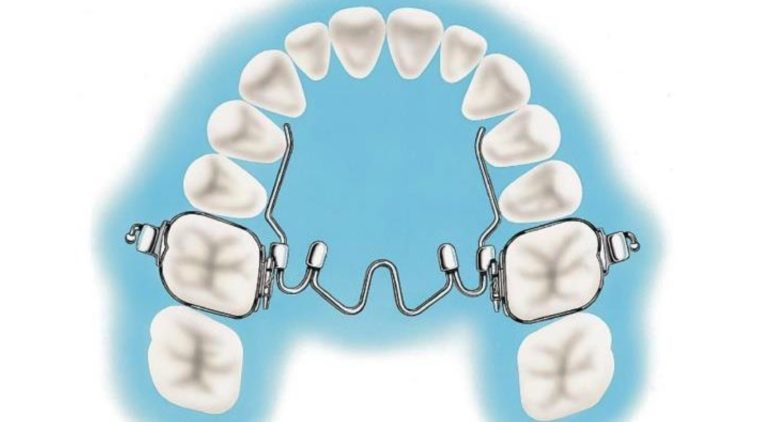

Tratamiento ortopédico de una maloclusión de clase III con mordida cruzada anterior profunda y discrepancia transversal

El artículo que compartimos el día de hoy con uds se llama Orthopedic Management of a Class III Malocclusion With Deep … [Leer más...] acerca de Tratamiento ortopédico de una maloclusión de clase III con mordida cruzada anterior profunda y discrepancia transversal